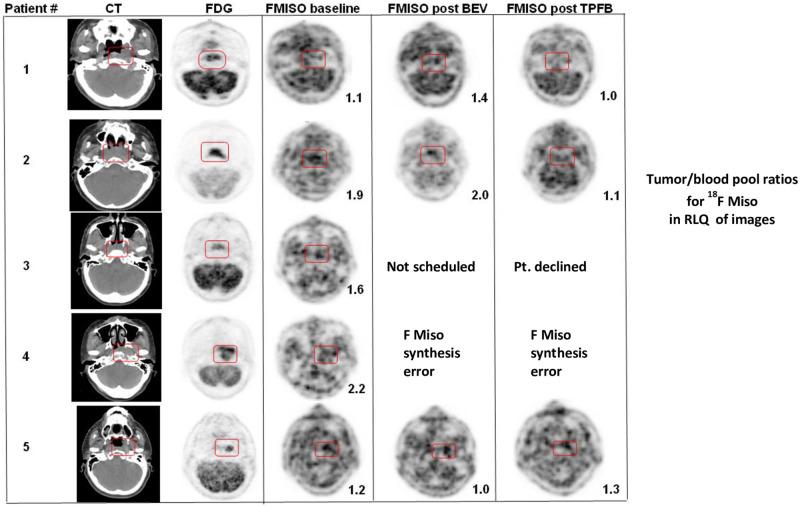

Twenty patients with LANPC (M0 cohort) and six patients with OMNPC (M1 cohort) received induction standard dose T (75 mg/m2) P (75 mg/m2) F (750 mg/m2 IVCI x 5days) x 3 followed by weekly cisplatin (40 mg/m2) or carboplatin (AUC 1.5) x 6 concurrent with radiation therapy of 70 Gy over 6.5-7 weeks. The first five patients received bevacizumab as part of an exploratory objective of hypoxia modification using correlative fluoromisonidasole (18F-MISO) PET CT scanning.

The 18F-MISO imaging failed to reveal adequate levels of baseline hypoxia necessary to evaluate for changes with chemotherapy and bevacizumab. Ninety percent of M0 patients and 83% of M1 patients received the full-intended TPF and radiation dose. Eighty-five percent of M0 patients and all M1 patients received at least 60% of the full-intended concurrent platinum dose. The 2-year progression free survival (PFS) rate for the M0 cohort was 90% (95% CI: 77.8%- 100%), and was sustained at 5 years. The 2-year PFS rate for the M1 cohort was 66.7% (95% CI: 37.9%- 100%). The 2-year overall survival (OS) rates for the M0 and M1 cohorts were 100% and 83.3% (95% CI: 58.3%- 100%), respectively. At five years, OS was 94.4% for the M0 cohort.

20 例 LANPC 患者(M0 队列)和 6 例 OMNPC 患者(M1 队列)接受诱导标准剂量 T(75mg/m2)P(75mg/m2)F(750mg/m2 IVCI x 5 天)x 3 随后每周顺铂(40mg/m2)或卡铂(AUC 1.5)x 6 与 70Gy 的放射治疗同时进行,共 6.5-7 周。前五例患者接受贝伐单抗作为使用相关氟米索硝唑(18F-MISO)PET CT 扫描进行缺氧修饰的探索性目标的一部分。

18F-MISO 成像未能显示出足够的基线缺氧水平,无法评估化疗和贝伐单抗的变化。90%的 M0 患者和 83%的 M1 患者接受了全剂量 TPF 和放射剂量。85%的 M0 患者和所有 M1 患者接受了至少 60%的全剂量同期铂类药物剂量。M0 队列的 2 年无进展生存率(PFS)为 90%(95%CI:77.8%-100%),并在 5 年内持续。M1 队列的 2 年 PFS 率为 66.7%(95%CI:37.9%-100%)。M0 和 M1 队列的 2 年总生存率(OS)分别为 100%和 83.3%(95%CI:58.3%-100%)。5 年时,M0 队列的 OS 为 94.4%。